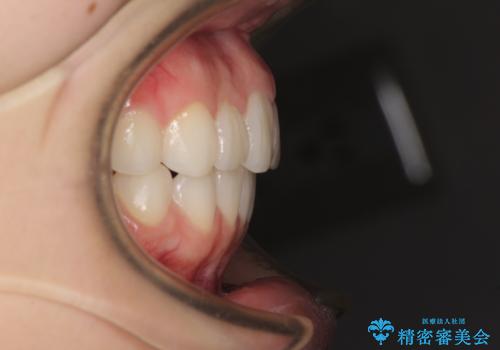

- デコボコと飛び出した前歯を治したいとのことで来院された患者様です。

ゴムかけを活用して上顎歯列全体を後方移動し、IPR(歯と歯の間を削る)によってデコボコが解消するように設計し、インビザラインにより治療を行うこととしました。

後方移動に際し、上下顎の親知らずは4本とも抜歯することとしました。

毎日しっかりと装着してくださったので、概ねシミュレーション通りに歯を移動させることができました。

治療前には接触することのなかった上下の前歯が接触するようになり、食事の際前歯でものをかみ切れるようになりました。